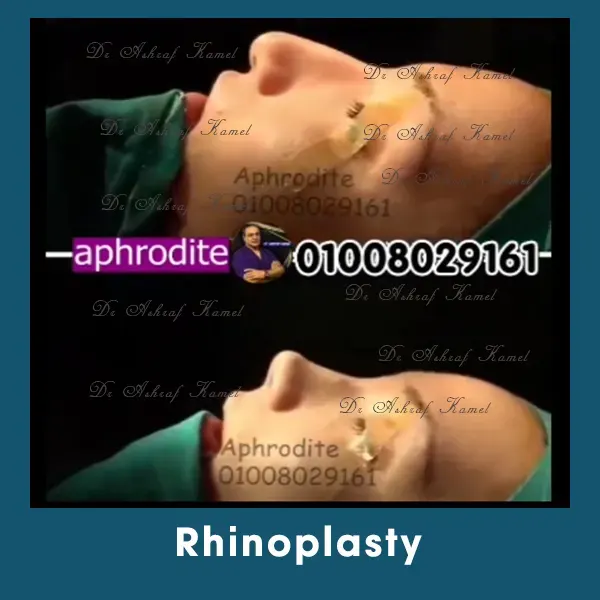

صور حالات مرضى

الخدمات

اشتهر بتقديم احدث تقنيات طب التجميل والجراحات التجميلية وعمليات تنسيق القوام، تكبير وتصغير وشد الثدي وتجميل الأنف وعلاج الترهلات، شد الذراعين و ازالة الترهلات، رفع الأرداف و علاج جراحات السمنة ونحت العضلات والـ6 باكس عالي التحديد، شفط الدهون بالفيزر والجي بلازما واحدث التقنيات بالخريطة الالكترونية، تجميل الجفون، تجميل الاذن وعلاج الاذن الوطواطية.